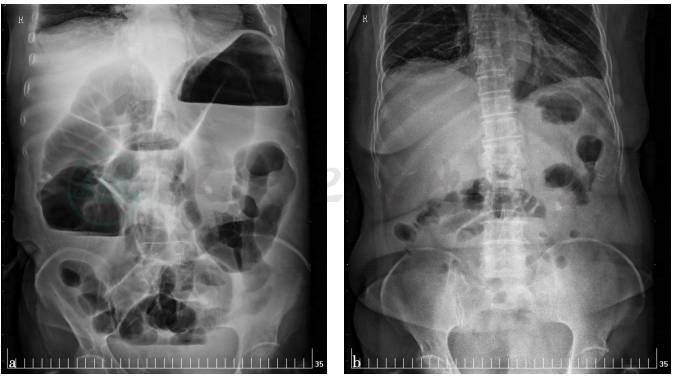

图2 全腹增强CT

厚,并腹腔多发淋巴结肿大,腹膜多发转移瘤,考虑肿瘤源于消化道;另见左肾结石,肝左外叶囊肿。但胃镜检查未见明显异常。(图1)

1)消化道恶性肿瘤:尤其是胃肠道肿瘤、肠道淋巴瘤。因患者肠梗阻明显,约1个月不能进食,体质虚弱,不能耐受肠镜、肠道CT检查,做了全腹增强CT检查,发现胃壁增厚、腹腔多发淋巴结肿大,腹膜多发结节,考虑转移瘤,需做胃镜检查,必要时做超声胃镜检查、腹腔镜活检。

(1)胃肠道肿瘤

患者血清及腹水的CEA均不高,全腹CT见胃壁增厚,肠壁无明显增厚,未见明显肿块,肠梗阻考虑为外压所致,且胃镜检查显示胃黏膜大致正常,胃壁充气撑开良好,胃壁蠕动良好,故消化道肿瘤诊断依据不足。